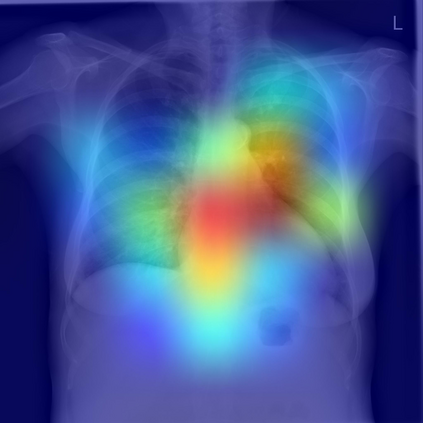

The remarkable success of deep learning has prompted interest in its application to medical imaging diagnosis. Even though state-of-the-art deep learning models have achieved human-level accuracy on the classification of different types of medical data, these models are hardly adopted in clinical workflows, mainly due to their lack of interpretability. The black-box-ness of deep learning models has raised the need for devising strategies to explain the decision process of these models, leading to the creation of the topic of eXplainable Artificial Intelligence (XAI). In this context, we provide a thorough survey of XAI applied to medical imaging diagnosis, including visual, textual, example-based and concept-based explanation methods. Moreover, this work reviews the existing medical imaging datasets and the existing metrics for evaluating the quality of the explanations. In addition, we include a performance comparison among a set of report generation-based methods. Finally, the major challenges in applying XAI to medical imaging and the future research directions on the topic are also discussed.